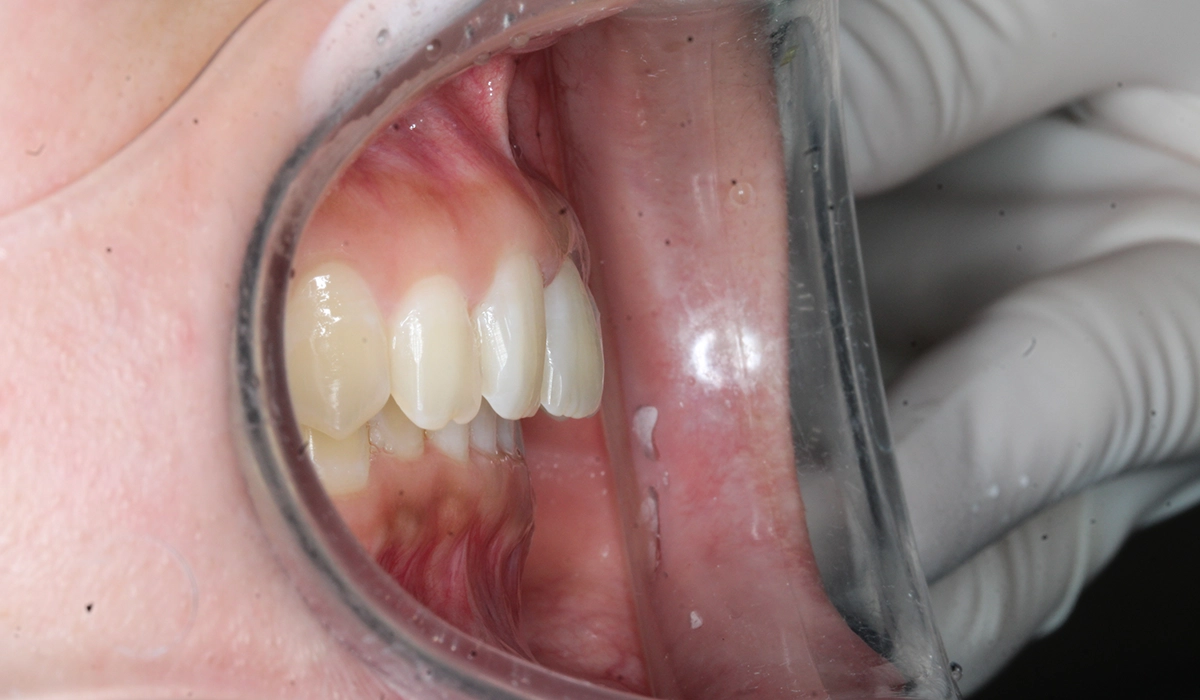

今回ご紹介する患者様は、前歯の噛み合わせの悪さ、歯並び、下の前歯が上の歯茎に当たることを気にされており、矯正検査後叢生Ⅰ級と診断いたしました。

術後:右側

術後:オーバージェット